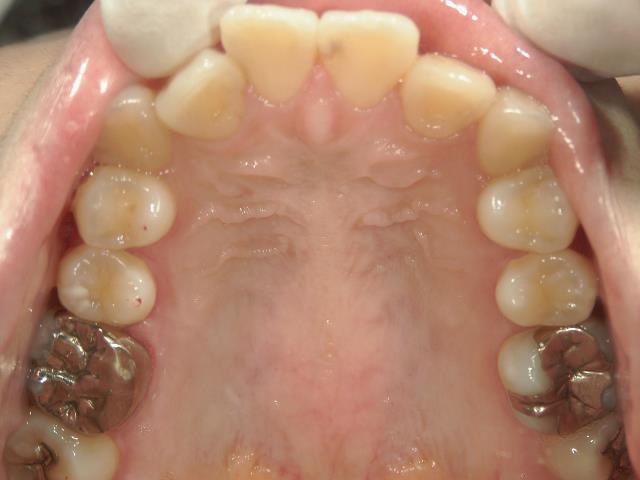

矯正歯科(全顎ワイヤー矯正)治療後

矯正歯科 治療後